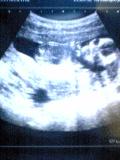

で、肝心のエコー写真がこの写真。

なんと!!

今回はばっちりお顔が写っています♪

わかります?? ややは横に寝ていて、右側が正面の顔です。

ちょっとエイリアンチックだけど(笑)

なんかアゴの線がえらく細い気がする。